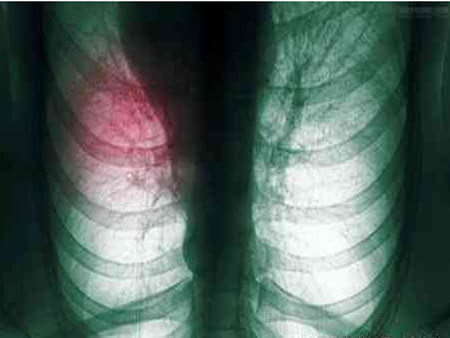

肺是人体器官中不可缺少的一部分,如里不好好爱护的话,一但发生癌变会给人们的呼吸带来很大的不利影响,而肺癌就是严重的肺部癌变,会给患者带来致命的威胁,需要尽早的接受治疗。那较为常见的肺癌的早期症状有哪些呢?康复乐园为大家讲讲较为常见的肺癌早期症状。